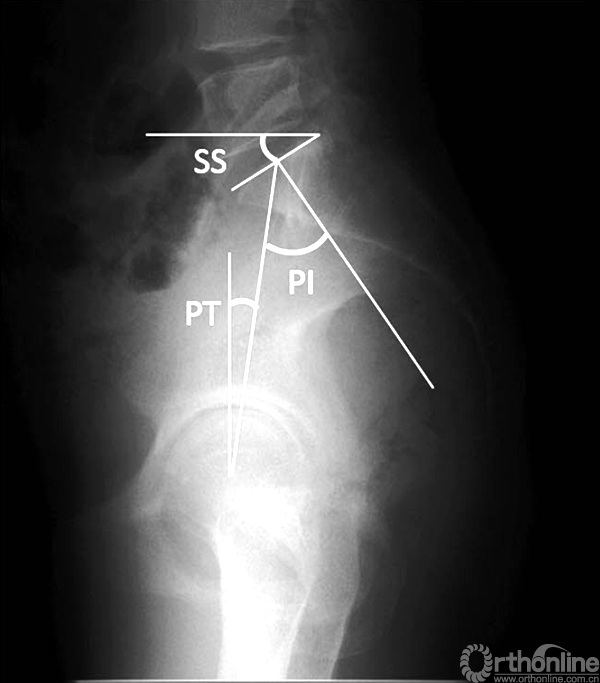

1998年Legaye等[4]提出骨盆投射角(pelvic incidence,PI)的概念,这一概念的提出,使骨盆在维持矢状位平衡中发挥的重要作用逐渐受到重视。

近10年来,脊柱骨盆矢状位平衡一直是脊柱外科的研究热点之一,围绕PI衍生出一系列的脊柱骨盆参数,其中最常用的包括骨盆倾斜度(pelvic tilt,PT)和骶骨倾斜角(sacral slope,SS)。骨盆相关参数与患者的健康相关生活质量(health-related quality of life,HRQOL)紧密相关[5]。

骨盆参数PI、PT、SS示意图

通过对健康人群的大样本测量分析,Schwab等[6]提出理想的腰椎前凸(lumbar lordosis,LL)与PI近似相等(LL = PI±9°)。而Jackson等[7]此前的研究结果则显示,正常情况下胸椎后凸(thoracic kyphosis,TK)与LL的比值TK/LL为0.15~0.75。

根据我们的经验TK应<LL-10°。矢状位曲线的完整性不仅仅反应在LL及TK的整体度数上,还与节段性的协调比例有关。生理状态下,下腰椎(L4~S1)的前凸约占腰椎整体曲线的2/3。[7]以水平线可将LL分为上弧和下弧,下弧曲度与SS的数值相等。若站立位L4椎体水平为LL的顶点,则下腰椎的前凸正好与SS相等,此时SS=2/3×LL。

而理想的PT值tPT(theoretical normal pelvic tilt,tPT)=0.37*PI-7°[8]。因此,通过测量患者术前的PI值,我们可以推导出相对理想的矢状位曲线。例如对于一个PI值为45°的患者,其理想的LL为45°,其中下腰椎LL为30°,TK应<35°,tPT=10°。